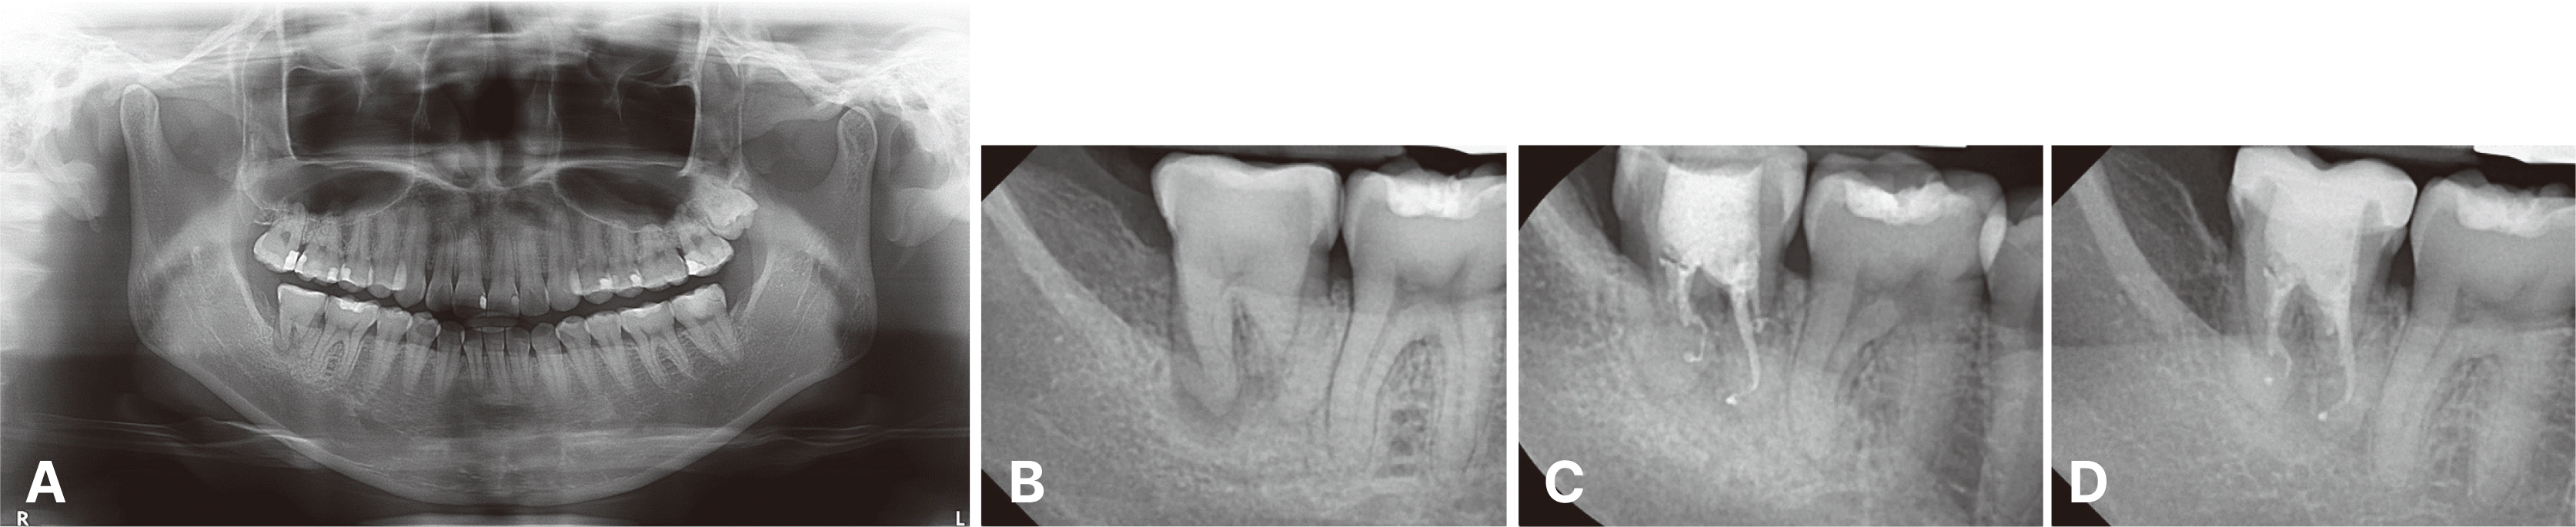

Fig. 1

Initial radiographic examination and pre-operative clinical status. (A) Initial panoramic radiograph showing the relationship between the donor tooth (incompletely erupted maxillary right third molar with approximately two-thirds root development) and the recipient site (mandibular right second molar). (B) Periapical radiograph showing extensive secondary caries under resin restoration extending to subcrestal level and periapical radiolucency in the distal root apex area of the mandibular right second molar. (C) Access opening for endodontic treatment revealed severe distal tooth structure loss extending subgingivally at the distal aspect of the mandibular right second molar.